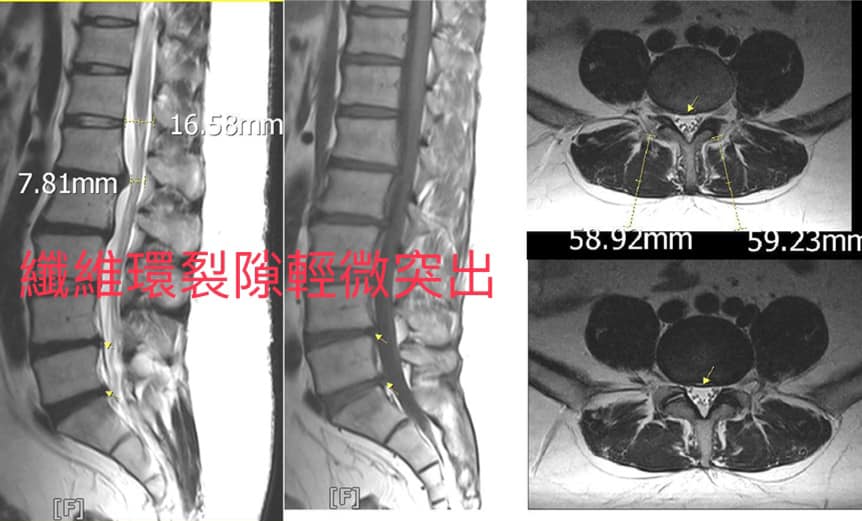

個案邱先生抱怨腰痛超過數年,一直到去年十一月惡化,做過傳統的復健治療跟打消炎針數次,最無法忍受的是沒辦法久站超過一個小時,有時候又會突然刺痛一下好像閃到一樣,最後求助於大醫院拍攝MRI,看到L4/L5,輕微突出,但纖維環有裂隙,導致突出髓核壓迫,但又不是非常嚴重到要馬上手術,所以這個問題一直困擾他。

治療結果:109/5/9~6/18 總計六周八次的治療,從原本站不到一小時就刺痛,改善到一次可以久站超過五小時以上,治療期間幾乎沒有發作了,囑咐患者繼續做減壓復健運動並觀察之,效果超乎預期